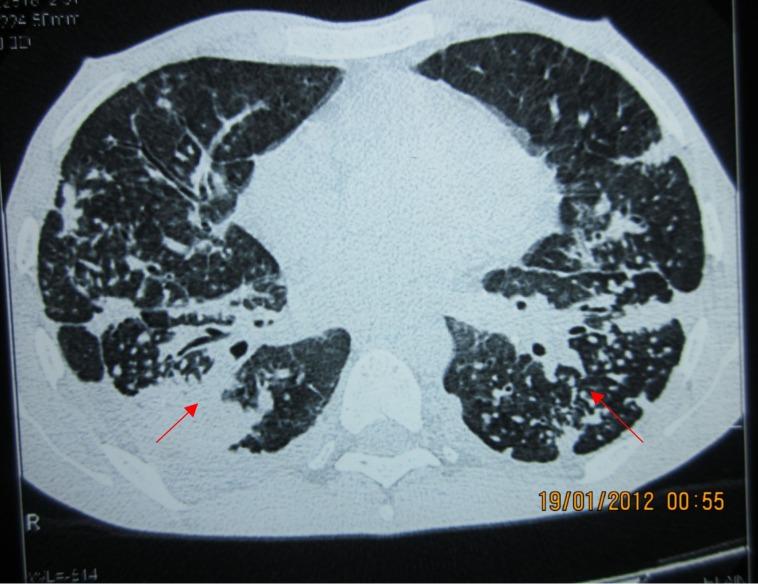

Several occupational hazards especially exposure to silica have been implicated as causal factors for the development of scleroderma-like disorders. Many case reports have documented the co-existence of silicosis and progressive systemic sclerosis in the same patient, mostly from European countries and also from Japan and the United States. We report a case of a 26-year-old male involved in stone masonry who developed silicosis-induced diffuse parenchymal lung disease and systemic sclerosis after exposure to silica dust. To our knowledge, it is the second case to be reported from India.

几种职业危害因素,尤其是接触二氧化硅,已被认为是硬皮病样疾病发生的致病因素。许多病例报告记录了同一患者同时存在矽肺和进行性系统性硬化症,这些病例大多来自欧洲国家,也有来自日本和美国的。我们报告一例26岁从事石匠工作的男性病例,该患者在接触二氧化硅粉尘后患上了矽肺引起的弥漫性实质性肺疾病和系统性硬化症。据我们所知,这是印度报告的第二例此类病例。